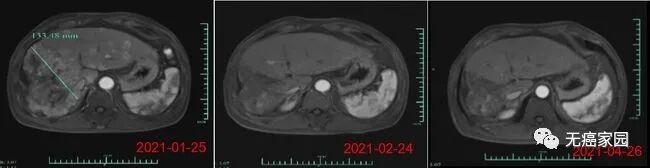

在数据截止时,受试者007的部分缓解时间6个月,其肿瘤体积在细胞治疗输注后1个月减少了80%以上。(截至2021年6月,该受试者已超过8个月的疾病控制,随访仍在进行中)。受试者012是1例弥漫型、巨块型晚期肝癌患者,曾接受过12次以上的TACE治疗、放疗及靶向治疗,不幸的是均无效,随后参与本研究。

在输注CAR-T细胞后的第28天,受试者MRI结果显示最大肿瘤直径从最初的133毫米减少至9毫米,缩小超过93%目前,该受试者正在接受CAR-T细胞输注后第3个月的评估,MRI扫描显示此肿瘤几乎消失。此外,甲胎蛋白(AFP,原发性肝癌的特定肿瘤标志物)水平从基线值 >80,000/ng/ml 下降到第1个月的1148.9ng/ml,并在第3个月下降到746.7ng/ml输注(正常范围<40ng/ml),证明 Ori-CAR-001 在晚期肝癌患者中具有显著的初步疗效。

图片

受试者012的MRI结果示意图